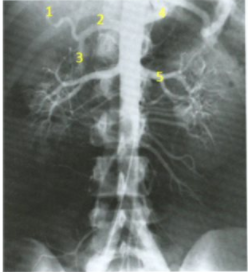

name the arteries

A

1. proper hepatic

2. common hepatic

3. gastroduodenal (1st branch off common hepatic)

4. splenic